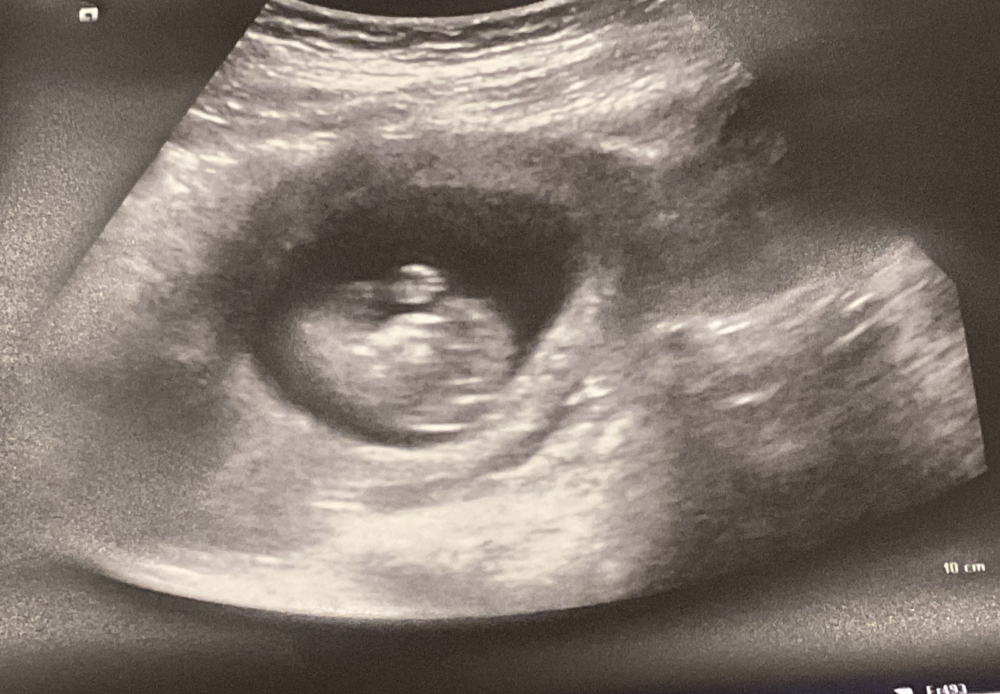

الحين انزل صور ان شاء الله واضحة

سونار اسبوع ١٢